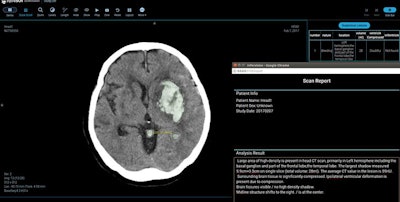

The deep learning-based software, called the AI-CT Stroke Screening System, is designed to help radiologists quickly determine the type, location, and severity of a stroke using a patient's brain CT scans, according to the company.

In patients with hemorrhagic stroke, the algorithm can accurately spot the location of the bleed and measure the amount of blood volume, the company said. As MRI scans are usually less available than CT studies, the AI-CT Stroke Screening System can also be used to help physicians detect signs of ischemic stroke on brain CT, providing more stroke information for clinical intervention, Infervision said.